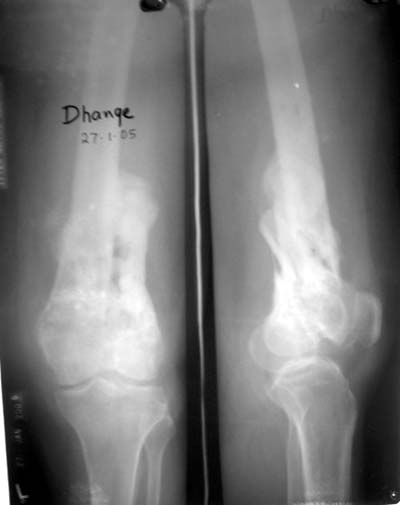

Качественные только исходные рентгенограммы (вышлю или завтра или в понедельник). Все последующие рентгенисследования были малоинформативны

(в т.ч. и последние снимки). КТ-исследование делалось 3 или 4 дня назад...

This is a coronal split in the femoral condyle and is a rare injury. Please see attachment for ORIF result

CT shows major bony fragments which are markedly rotated .With this amount of bony damage,you probably should attempt to get reasonably loooking knee with ORIF and thn if he needs a TKR due to pain a few years from now, then tleast you have something looking like a knee that you can replace rather than having to use revision knee for a primary TKR now. 4 weeks is not too long .what is the condition of soft tissues?

Before the CT and MRI era, we were treating the fractures with study of the Xrays alone. Such fractures with skeletal traction followed by non wtbearing mobilisation used to yield a fairly good range of movements. The CT gives a real ghastly picture of not so bad looking plain Xrays. I think this case needs traction to start with to correct the flexion deformity which probably will be achieved in 2 weeks time or less. We can then reassess the case with fresh Xrays. If possible one should try and fix the fragments to get some alignment. But the fixation should be stable enough to be able to mobilise the joint. Otherwise the traction can be continued for another 2 weeks to make the fracture sticky and then mobilise. We could get about 70 to 80* movements in spite of such communition. I am enclosing an Xray of a patient who is walking independantly and has 0 to 80* movemnts of the knee for the last one year

Фронтальные внутрисуставные переломы мыщельков бедра, так называемые Hoffa fracture, не частые, но встречающиеся переломы, в основном они связаны с травмой высокой энергией.

В зависимости от смещения рекомендуется сопоставление костных фрагментов с последующей жесткой фиксацией.

В вашем случае доступ будет медиальный, сопоставить развернутый медиальный мыщелок и фиксацию надо произвести в передне-заднем

направлении шурупами 4.5 мм в диаметре, углубив головку шурупов под хрящ, а поперечную фиксацию - межмыщелковыми шурупами. Желательно применить шурупы 6.3 мм в диаметре. Дополнительная Buttress technique пластина предотвратит перелом от скольжения.

Даже при сросшемся переломе мыщелка рекомендуется реконструктивная операция для предотвращения последующих варус или вальгус деформации.

Место образовавшего костного дефекта после разворота мышелка заполняется спонгиозной аутокостью. Костная пластика применяется даже

в свежем случае.

Под наркозом редрессация, ранняя разработка сустава после операции, нагрузка на конечность через 12 недель помогут удержать без коллапса

фиксацию и поможет больному восстановить функции конечности без артропластики коленного сутава.